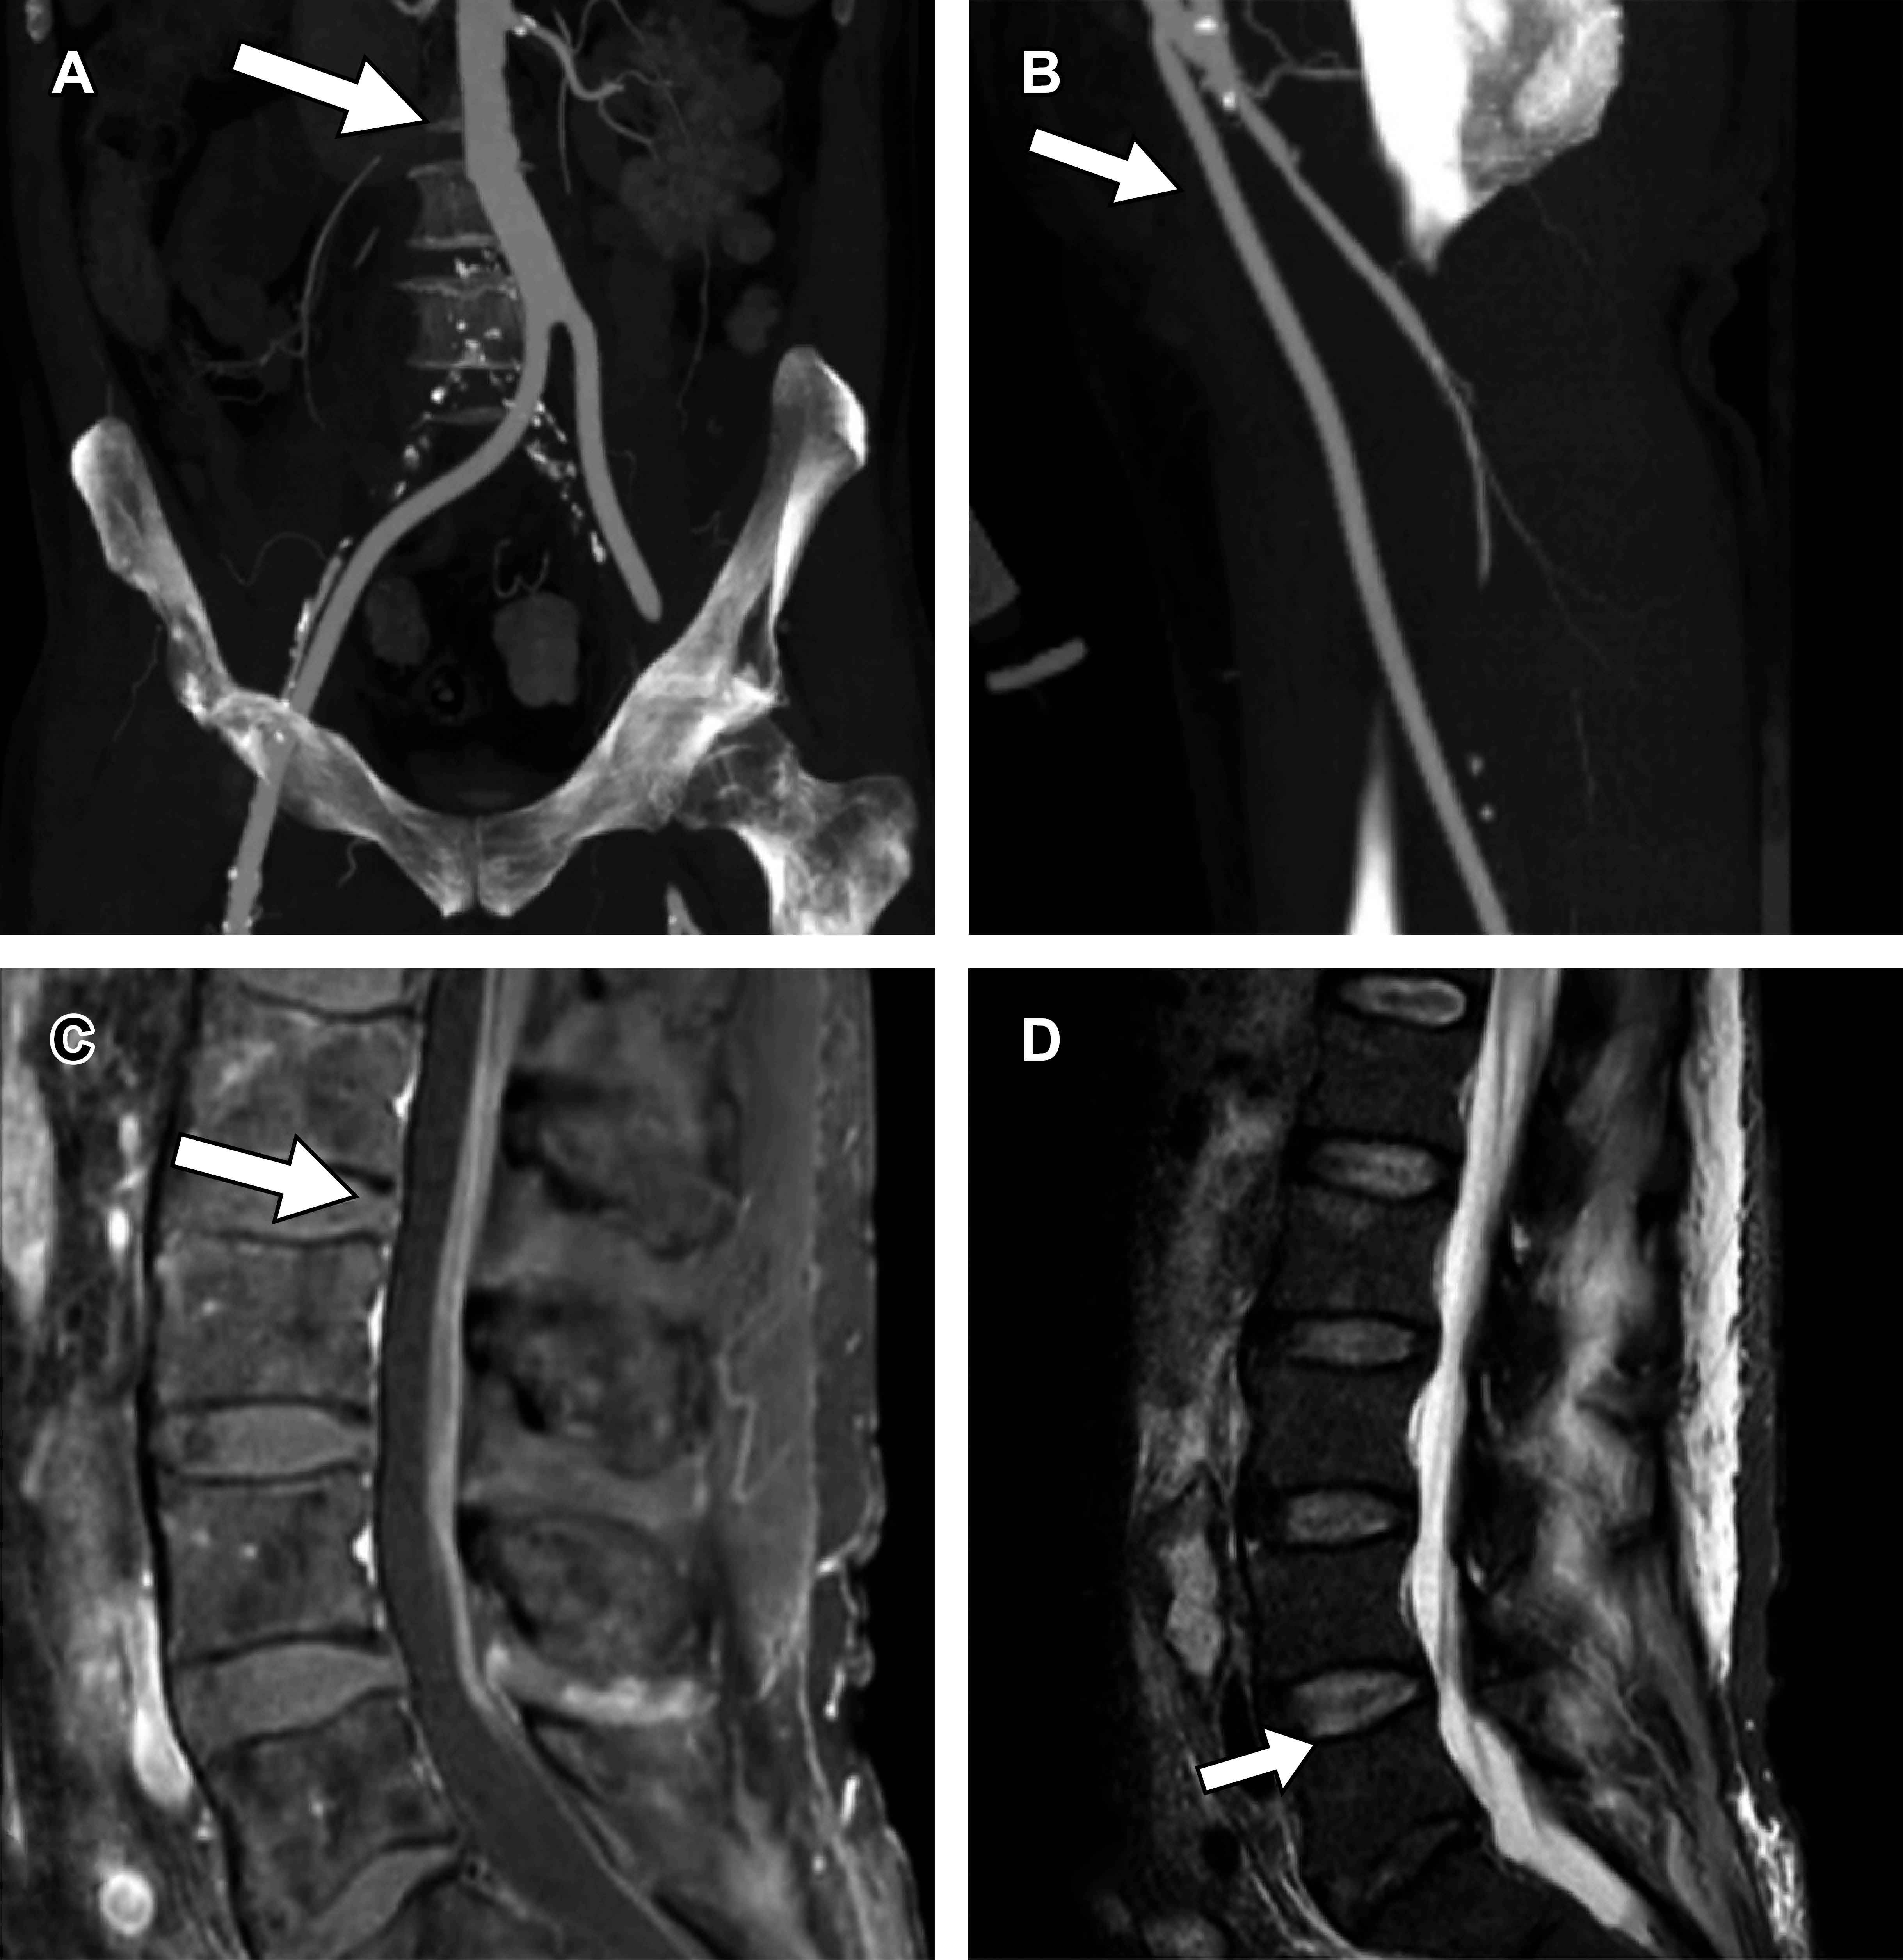

A pesar del pinzamiento aórtico breve y del manejo transoperatorio óptimo, el injerto colocado en el segmento infrarrenal L2-L3, junto con la variante anatómica de emergencia ectópica de la arteria del cono o Desproges-Gotteron —dependiente de la rama iliolumbar de la arteria iliaca interna—, podría resultar insuficiente para garantizar la irrigación medular ante cualquier alteración en la perfusión. Al igual que en el flujo sanguíneo cerebral, la vasorregulación de la médula espinal depende del pH y de la pCO2. La isquemia desencadena una respuesta inflamatoria y excitotoxicidad, predominantemente mediante apoptosis controlada (Figura 3A).3

Asimismo, el paciente presentó una importante colateralidad de predominio sistémico por medio de arterias hipogástricas, iliolumbares y sacras como origen de las arterias radiculares que no compensan en el segmento inferior (Figura 3B). Está descrito el drenaje de líquido cefalorraquídeo como un método de protección para la isquemia medular; Bertoni y colaboradores mencionan una serie de protección medular solo en pacientes donde se cubrió toda la aorta torácica, y en caso de abordar la aorta abdominal solo si la aorta torácica había sido intervenida previamente, por lo que como medida profiláctica está fuera de escenario.4

Figura 3